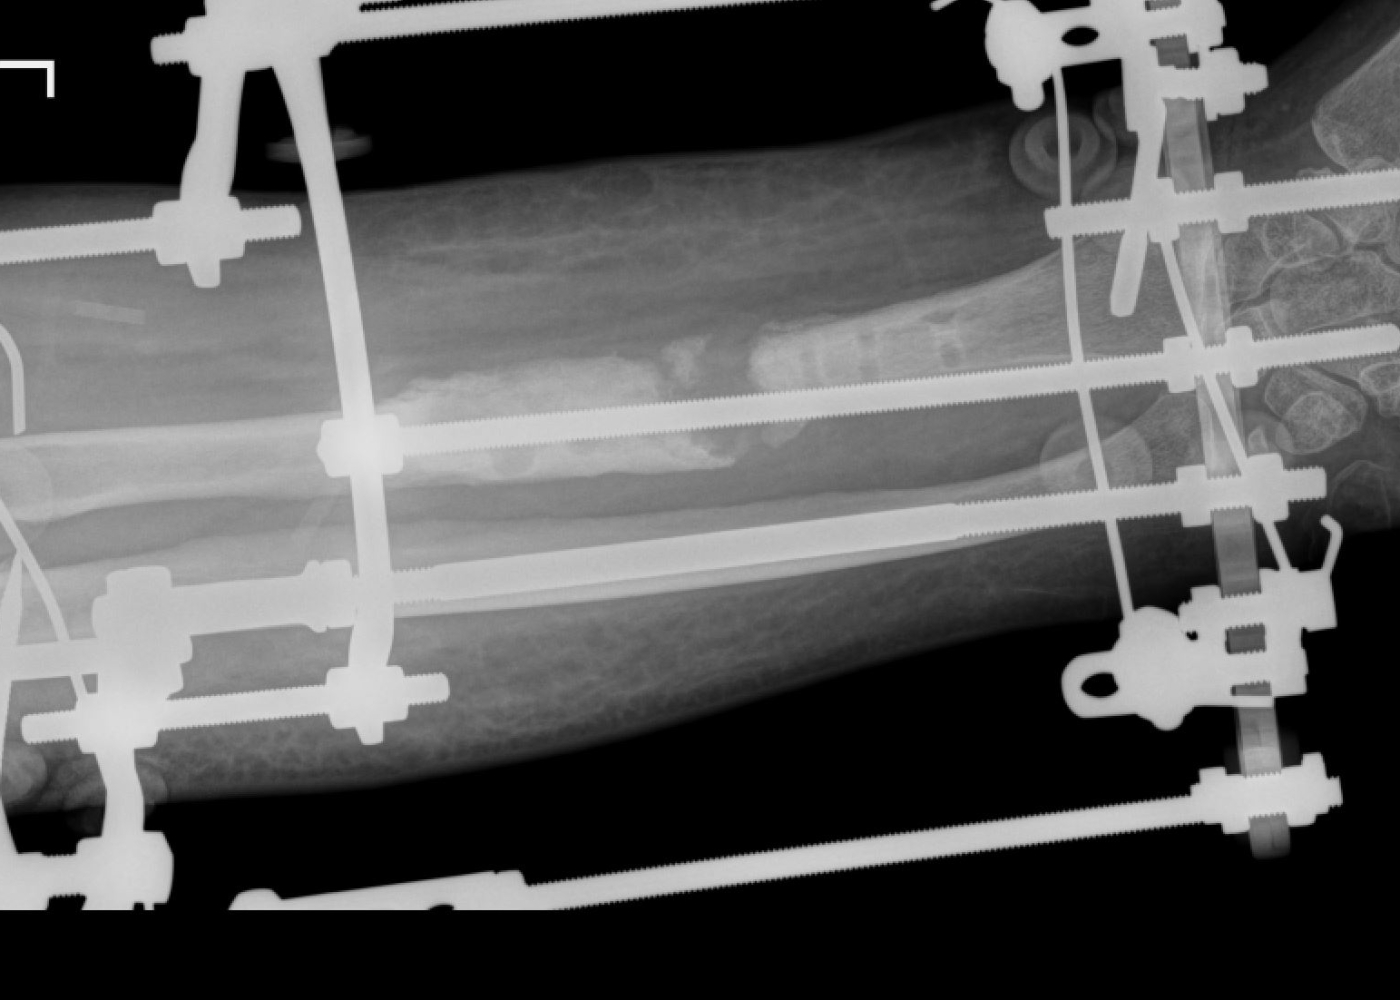

Որոշվել է վիրաբուժական ռազմավարությունը՝ բաղկացած երկու փուլից։ Առաջին փուլով Օրթոպեդիայի և վնասվածքաբանության բաժանմունքի վարիչ Սեյրան Սարոյանի կողմից կատարվել է ձախ նախաբազկի երկարեցում Իլիզարովի ապարատով, որը միտում ուներ նախ շտկել նախաբազկի կարճացման հետևանքով առաջացած հոդախախտը, ապա ապահովել փոքրացած և կարկամված մկանների և ջլերի էտապային, դանդաղ, անցավ երկարացումը։ Առաջին վիրահատության արդյունքում բուժառուի նախաբազուկը հաջողվել է երկարացնել մոտ 4 սմ-ով։